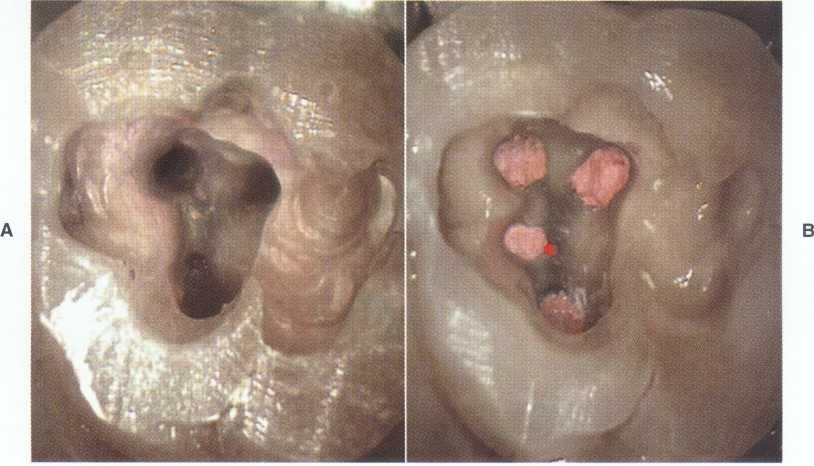

FIGURE 2-13 A, Removal of the amalgam permits inspection of the tooth for fractures. The use of microscopy allows identification of a mesiodistal fracture. The pulp chamber has not been entered. B, On entering the pulp chamber, the clinician notes a fracture across the pulpal floor from mesial to distal. Wedging a Glick instrument into the access allows the clinician to visualize the fracture spreading and closing in this hopeless tooth. Although this gross fracture was visible with loupes, the extent of many fractures cannot be seen. Diagnosis and prognostication then become guessing games at best. Note the white dot of the MB2 canal located (in vain) with a Mueller bur above the fracture about halfway between the fracture and the MB canal; this was not visible without the microscope.